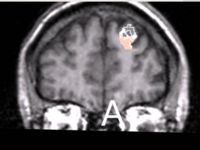

We are developing rule-based segmentation techniques which speedup the process and improve the accuracy for delineating the DLPFC in brain MRI scans. Our objective is to develop Slicer modules to facilitate clinical use of these techniques.

Our approach for segmenting the DLPFC is described in the references below. The challenge is to make this software user-friendly to enable clinical use of the tool. Our plan for the week is to fix/add several features to improve the user experience.